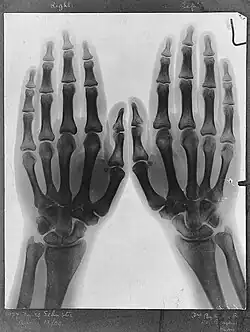

![]() X-ray of Norah Schuster's hands taken by her father.[1] | |

Norah Schuster was born on 14 July 1892, the daughter of the German-born British physicist Arthur Schuster who was the first to report the findings of Wilhelm Röntgen about X-rays in the United Kingdom.[3] Later in life, Norah described her father's initial uses of bedside X-rays taken in Manchester in 1896.[4] He gave public lectures on the new technique which Norah and her brother attended, X-rays of their hands and feet being used to illustrate the proceedings for which a ten minute exposure was required due to the weakness of the rays.[5]